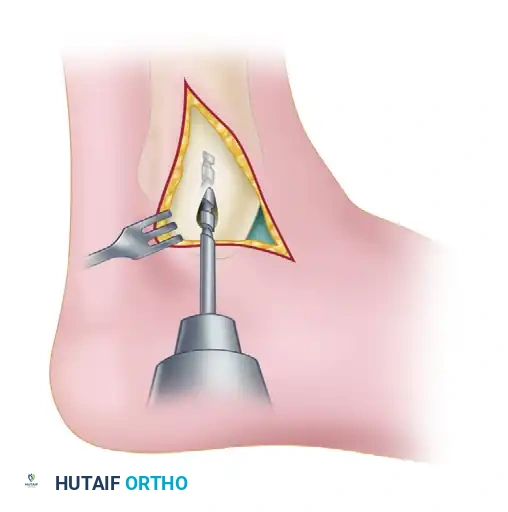

Open Medial Malleolar Osteotomy

When large, posterior-medial lesions require structural grafting (OATS) or direct fixation, an open approach via medial malleolar osteotomy is required.

- Incision: A longitudinal incision is made over the medial malleolus.

- Pre-drilling: Before the osteotomy, two parallel holes are drilled from the tip of the medial malleolus proximally into the tibial metaphysis. These are tapped for 4.0-mm cancellous screws to ensure perfect anatomic reduction during closure.

- Osteotomy: A chevron-type (V-shaped) osteotomy is performed using an oscillating saw, directed toward the axilla of the medial clear space. The osteotomy is completed with an osteotome to preserve bone dust and create a rough surface for healing.

- Exposure: The medial malleolus is reflected inferiorly on its intact deltoid ligament hinge, exposing the medial talar dome.

- Lesion Management: The lesion is addressed (e.g., OATS procedure).

- Closure: The malleolus is reduced and secured with the previously selected screws.